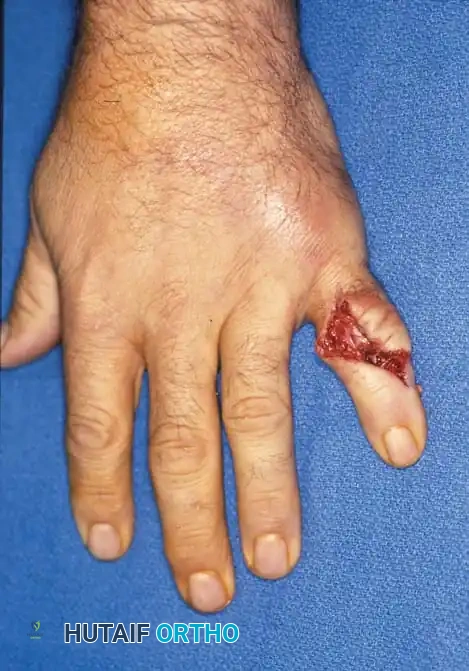

When multiple digits are involved, or when fractures are open, highly comminuted, or associated with soft-tissue loss, operative stabilization is mandatory. The goal is to achieve skeletal stability that permits early active range of motion (ROM), thereby preventing the dreaded complication of tendon adhesion and joint stiffness.

Open or severely comminuted fractures of the phalanges may be unsuitable for internal fixation using traditional plates or screws, as the hardware may further fragment the bone or require excessive soft-tissue stripping.